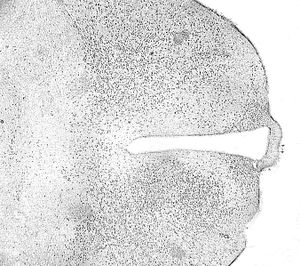

- BrdU: used to identify replicating cells. Used to identify tumors as well as in neuroscience research.[11]